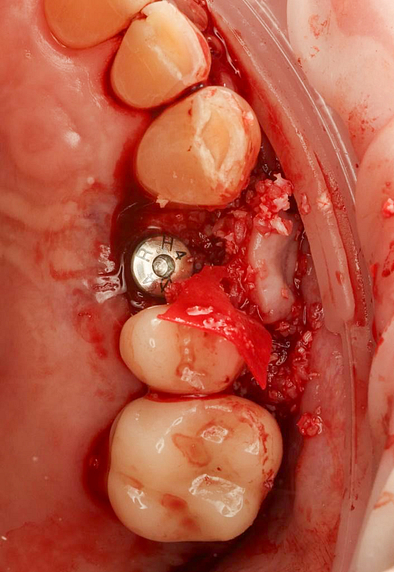

A custom surgical guide was designed and 3D printed, incorporating all the critical information from the virtual planning. The implant surgery was performed under local anesthesia, with the surgical guide firmly in place to ensure accurate implant placement. Bone grafting was performed to address the bony defect and promote optimal healing.

The Osstem OneGuide kit is used with a fully guided osteotomy and implant placement.

Osstem TSIII D4 x H10mm implant on NoMount driver.